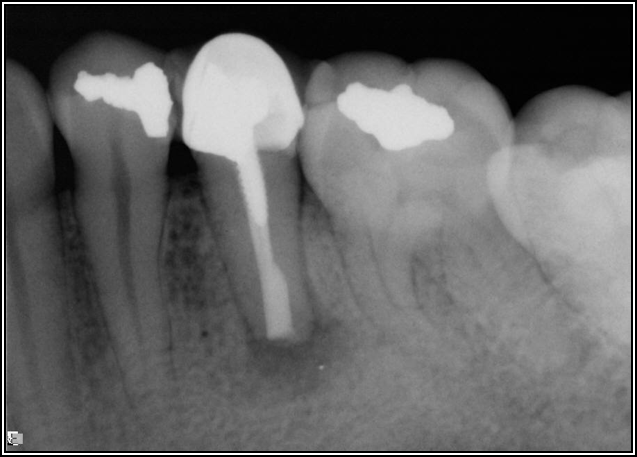

Occlusion is one of the most overlooked areas in endodontics; however, other than remaining structure, it is the most important factor.7 Patients who are heavy bruxers can cause the need for a root canal from the lateral forces. Patients who clench pose a different challenge with apical forces, yet the damage from both can be the same. Figure 7 shows a patient with bruxism. The patient had pain in response to hot and cold stimulus, and the clinicians needed a bitewing to determine which tooth was causing the pain. From the periapical (PA), it was clear that tooth No. 2 had a large problem, No. 3 had a crown, and No. 4 had a large restoration. Any of the three may have been the source of the problem.

With the bitewing shown in Figure 8, it became clear there was gross decay in tooth No. 3 that could not be seen on the PA, and there was a periodontal defect, a pulp stone, in No. 2. There was also a class V lesion revealing the bruxism, flat occlusion, multiple restorations in No. 30, a post in No. 31, and decay on No. 2 as well. The post in No. 31 was useless because when a post is placed, it must be the right length, width, and size. If the post is too short, there will be a greater fulcrum and the tooth will break. If it is too long, the clinician can break it by wedging it. If it is too short, it will not hurt the tooth, but it will not provide any valuable function. It is overall preferable to do posts in teeth having just single restorations rather than abutments for bridges because those teeth are already under greater force. If the technique is not performed correctly, iatrogenic issues may result.

Fig 7. Bruxism.

Figure 7

Fig 8. Bitewing revealed decay and other problems.

Figure 8